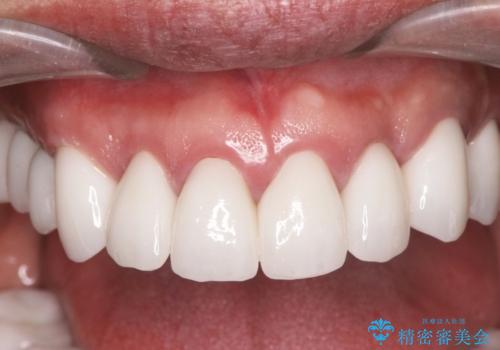

セラミッククラウンを除去し仮歯を装着し、歯周外科手術を行い歯ぐきの状態を改善したのち、適合の良いセラミッククラウンを再作製をする治療計画としました。

- 90.2万円(ジルコニアクラウン×6・仮歯×6 ・歯周外科手術)費用は治療当時の料金となります